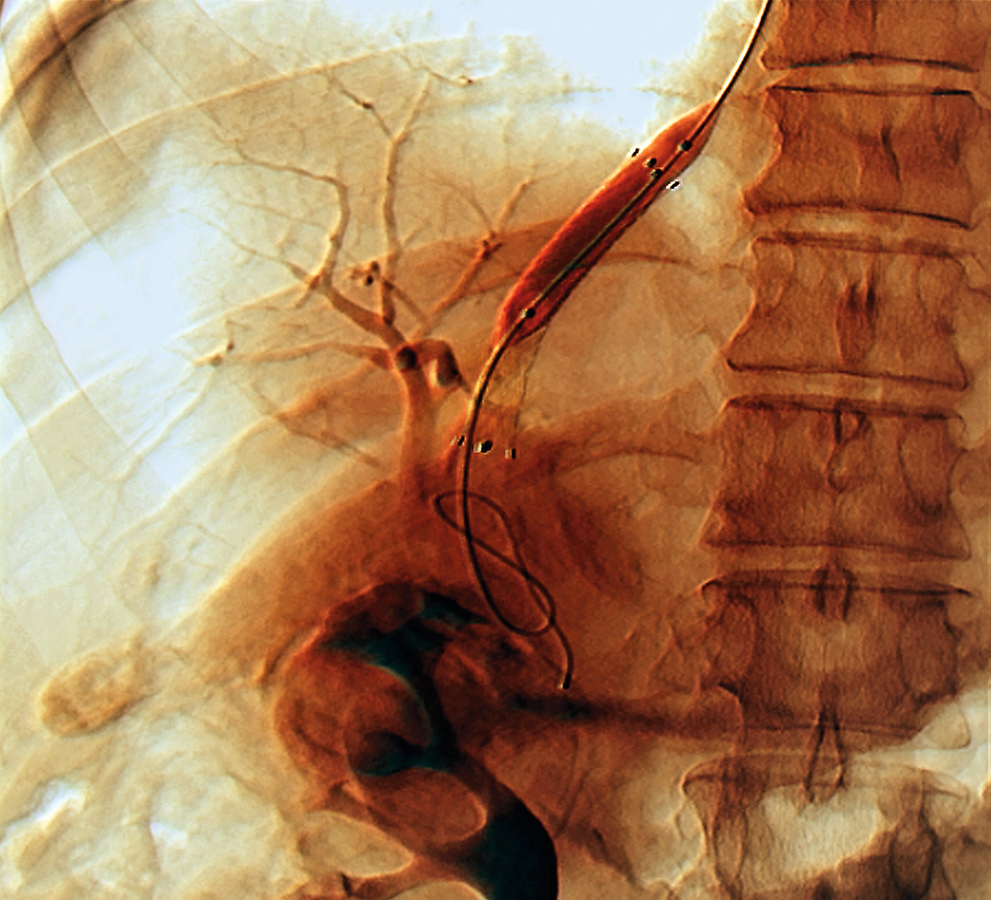

Bei Leberzirrhose sollte man frühzeitig die Implantation eines transjugulären intrahepatischen portosystemischen Shunts (TIPS) erwägen. Bei Leberzirrhose sollte man frühzeitig die Implantation eines transjugulären intrahepatischen portosystemischen Shunts (TIPS) erwägen. © Science Photo Library/Zephyr

Einbringen des Stents erfolgt unter Ultraschallkontrolle

Die Anlage des TIPS erfolgt mittels Katheter über einen transjugulären Zugang. Mithilfe einer Punktionsnadel wird unter sonographischer Kontrolle eine Verbindung zwischen einer Lebervene und einem Ast der Pfortader geschaffen. Durch die Nadel lässt sich ein Führungsdraht bis in die V. mesenterica superior oder die V. lienalis vorschieben. Anschließend wird ein Katheter eingebracht, der eine Kontrastmitteldarstellung der Pfortadergefäße nebst etwaiger Umgehungskreisläufe ebenso ermöglicht wie die Kontrolle der Druckverhältnisse. Schließlich schiebt man einen Stent in den neu geschaffenen Kanal vor und dilatiert so lange mit einem Ballon, bis der portosystemische Druckgradient unter 12 mmHg liegt.